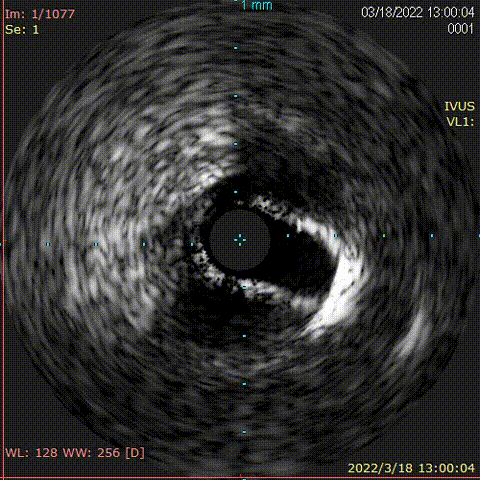

对前降支行IVUS,钙化较重,超声导管通过困难

旋磨后行IVUS查看,钙化较前明显减轻